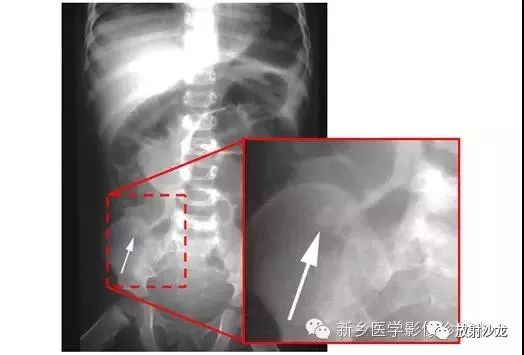

上图腹部平片检查是一6岁男孩,出现呕吐和急性右髂窝疼痛进行的。两个关键的发现在哪里?(提示:通过放射科医生所提供的箭头可以缩小关注点。)

右髂窝多个扩张的小肠襻出现小的钙化结节。小肠袢可与大肠区分开来,因为小肠的环状襞延伸至整个肠壁,而结肠袋只是部分延伸存在。在右下腹(箭头)的钙化结节高度提示阑尾粘连。这个病人开腹手术发现阑尾粘连致小肠梗阻。